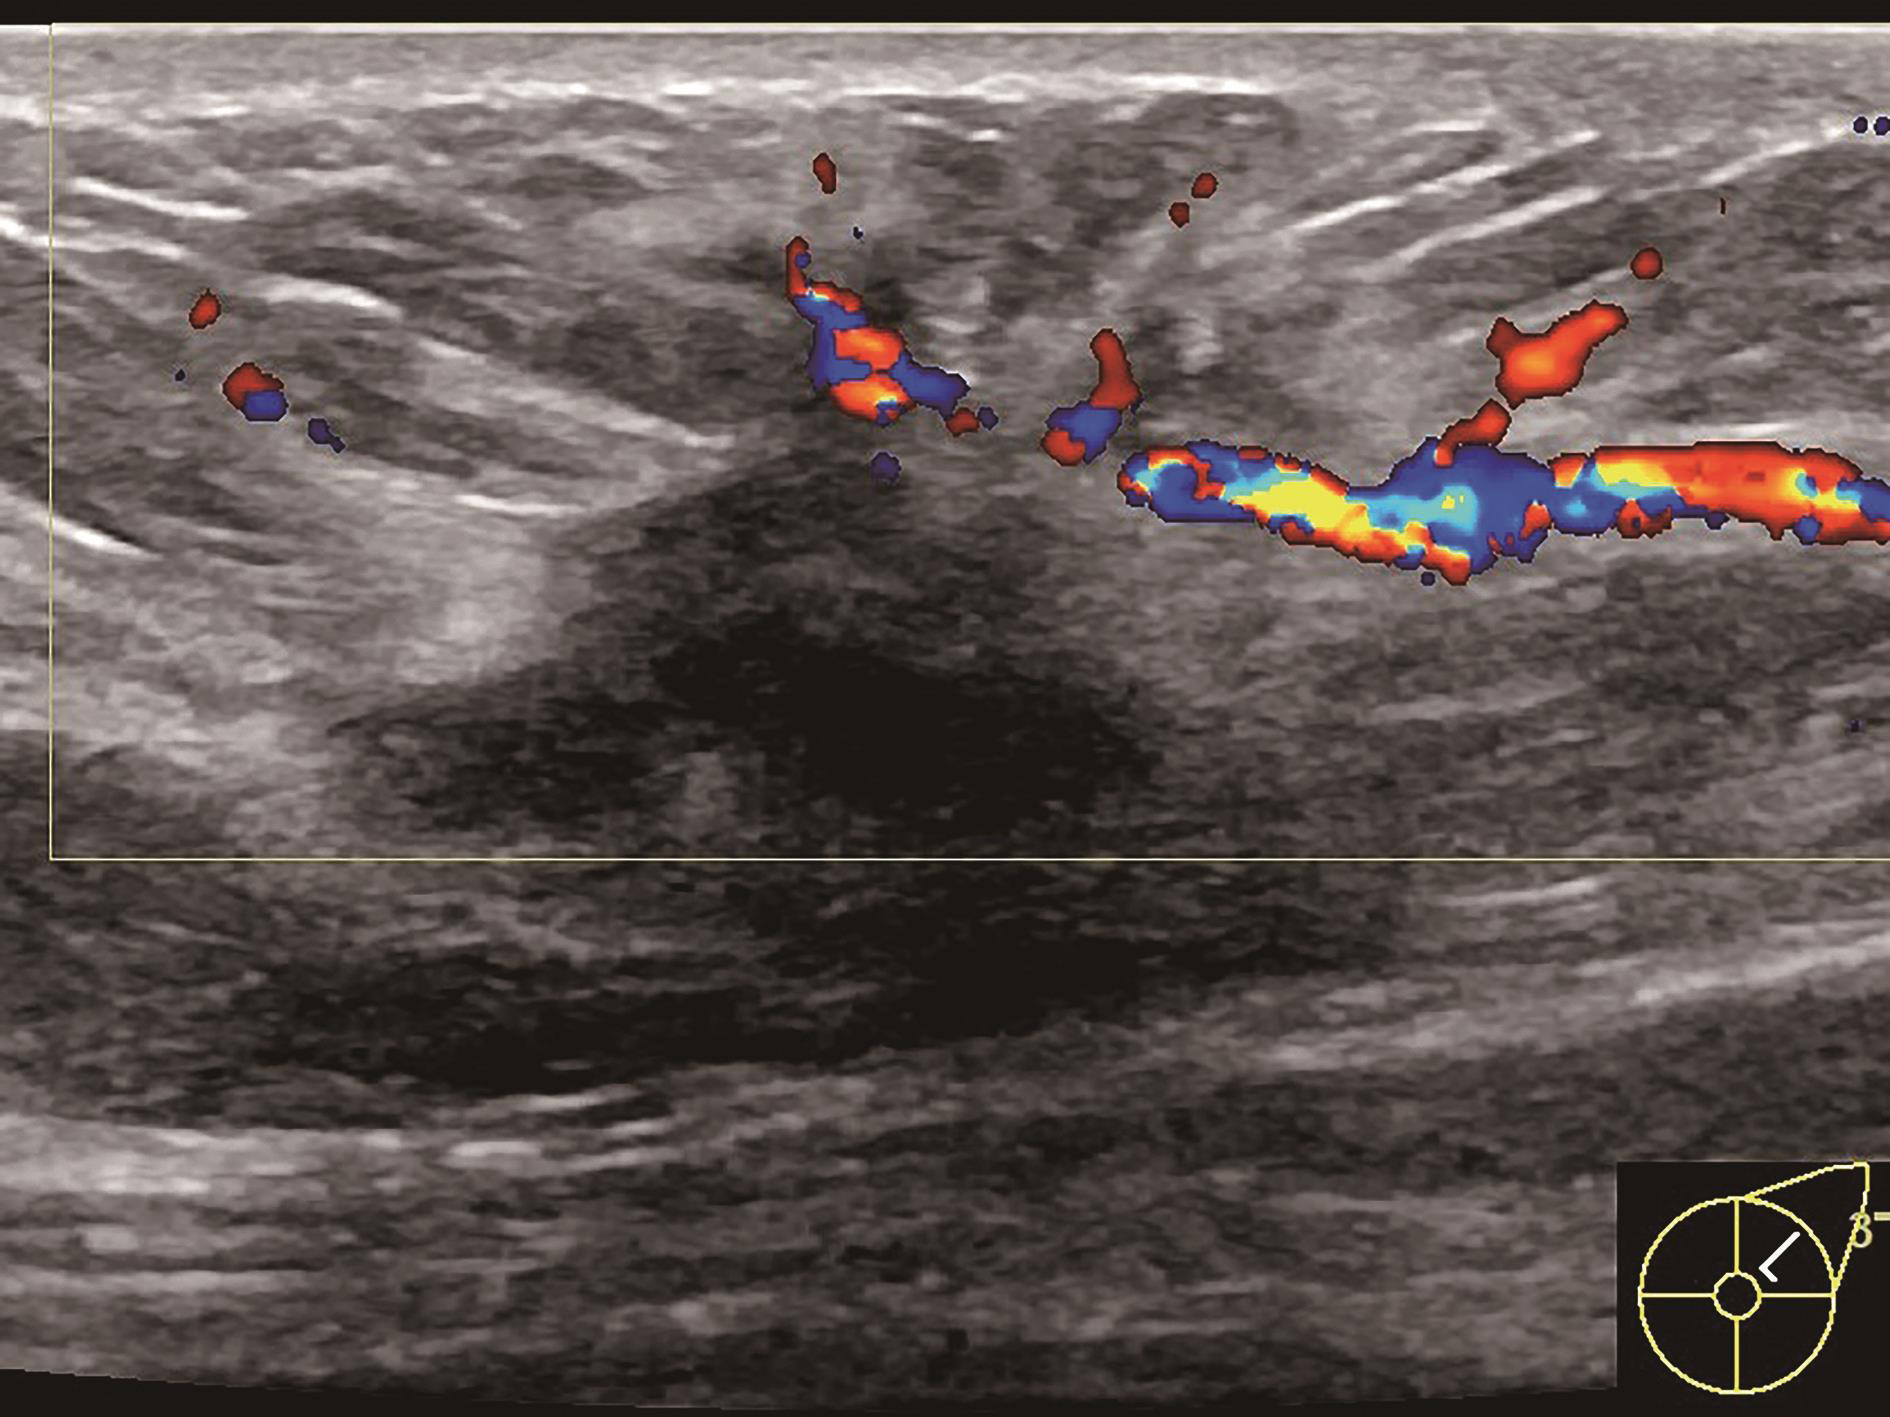

图2-2-1 确定造影病灶

A.病灶二维图像;B、C.病灶CDFI图像;D.同侧腋窝淋巴结情况;E.病灶弹性成像图像

造影前应用传统灰阶超声全面扫查患侧乳腺及腋窝,重点扫查既往检查可疑病灶所在象限,结合既往检查确定超声造影靶目标及造影切面。评估病灶所在部位乳腺腺体致密性,二维及彩色多普勒(CDFI)超声常规检测肿块的大小、形态、边界、内部回声、血流及与周边组织的关系,充分利用现有超声新技术(如弹性成像)全面评估病灶。当病灶位置表浅、位于乳头后方或与探头耦合不佳时,可应用超声垫。

图2-2-5 血流信号最丰富或有滋养血管切面